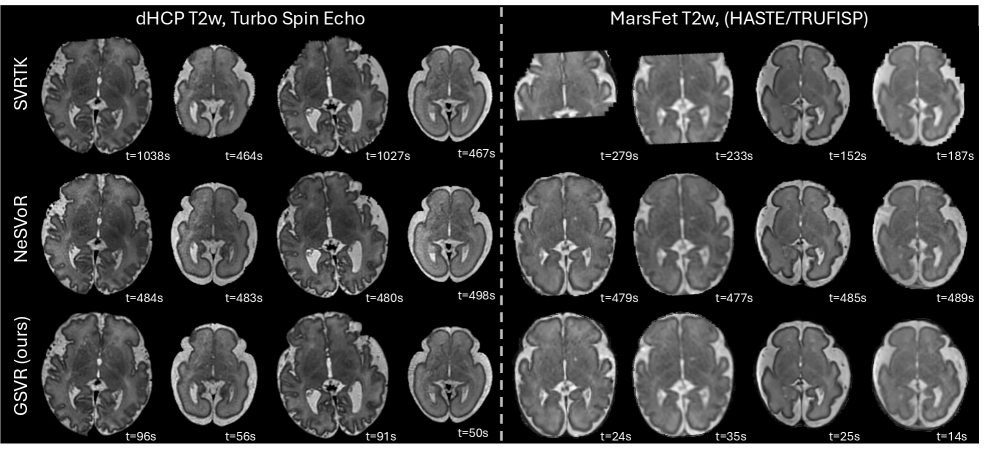

Qualitative Evaluation on In-vivo Data: \figurereffig:qualitative_invivo_dhcp shows reconstructions on real-world clinical scans from the dHCP and MarsFet datasets. SVRTK reconstructions often exhibit field-of-view (FOV) cut-offs, failing to recover the complete brain due to masking failures or incomplete FOV in the raw acquisitions. Both NeSVoR and GSVR successfully recover coherent, high-resolution isotropic 3D volumes. Our method resolves fine anatomical structures, such as the cortex, with a level of sharpness comparable to NeSVoR. The visual results further confirm the efficiency gains of GSVR demonstrating speed-ups of up to factor 10 over NeSVoR an SVRTK without compromising reconstruction quality.

fig:qualitative_invivo_dhcp